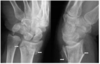

Décrire la fracture

- Fracture comminutive extra-articulaire de la métaphyse proximale de l’humérus gauche avec déplacement en valgus.

- Arrachement osseux de la grosse tubérosité